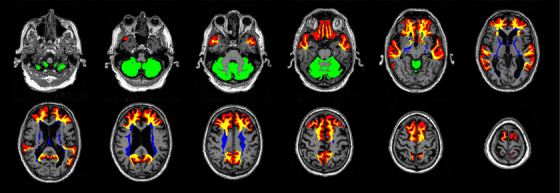

Abstract Image